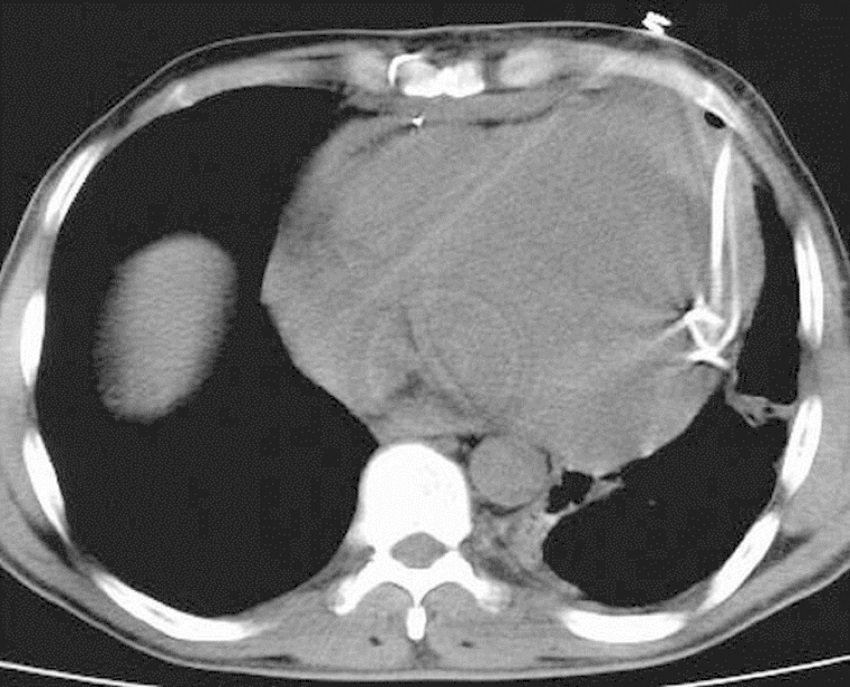

Having been colored and disinfected, the marked area was covered with sterile drapes. As a local anesthetic agent, 2% lidocaine was used. Then, an 18 G needle with negative puncture was entered to the pericardial cavity, the needle was fixed at the level of liquid aspiration, and the CT was taken again to reaffirm the needle's position (Figure 2). After confirming that it was in the intrapericardial space, the liquid was aspirated and evaluated. If hemorrhagic characteristics were thought to be possible after confirming that the blood defibrinated, a 0.035" guidewire was sent to the pericardial cavity through the needle (Figure 3). The needle was removed and the CT was taken; after confirming that the guidewire was in the intrapericardial cavity, an 8 or 10 F nephrostomy catheter was advanced into the pericardial cavity through a catheter guide. A three-way tap was installed in the tip of the catheter and the liquid was poured into a 50 ml syringe. The catheter was identified and it was connected to the closed underwater drainage system (Figure 4).